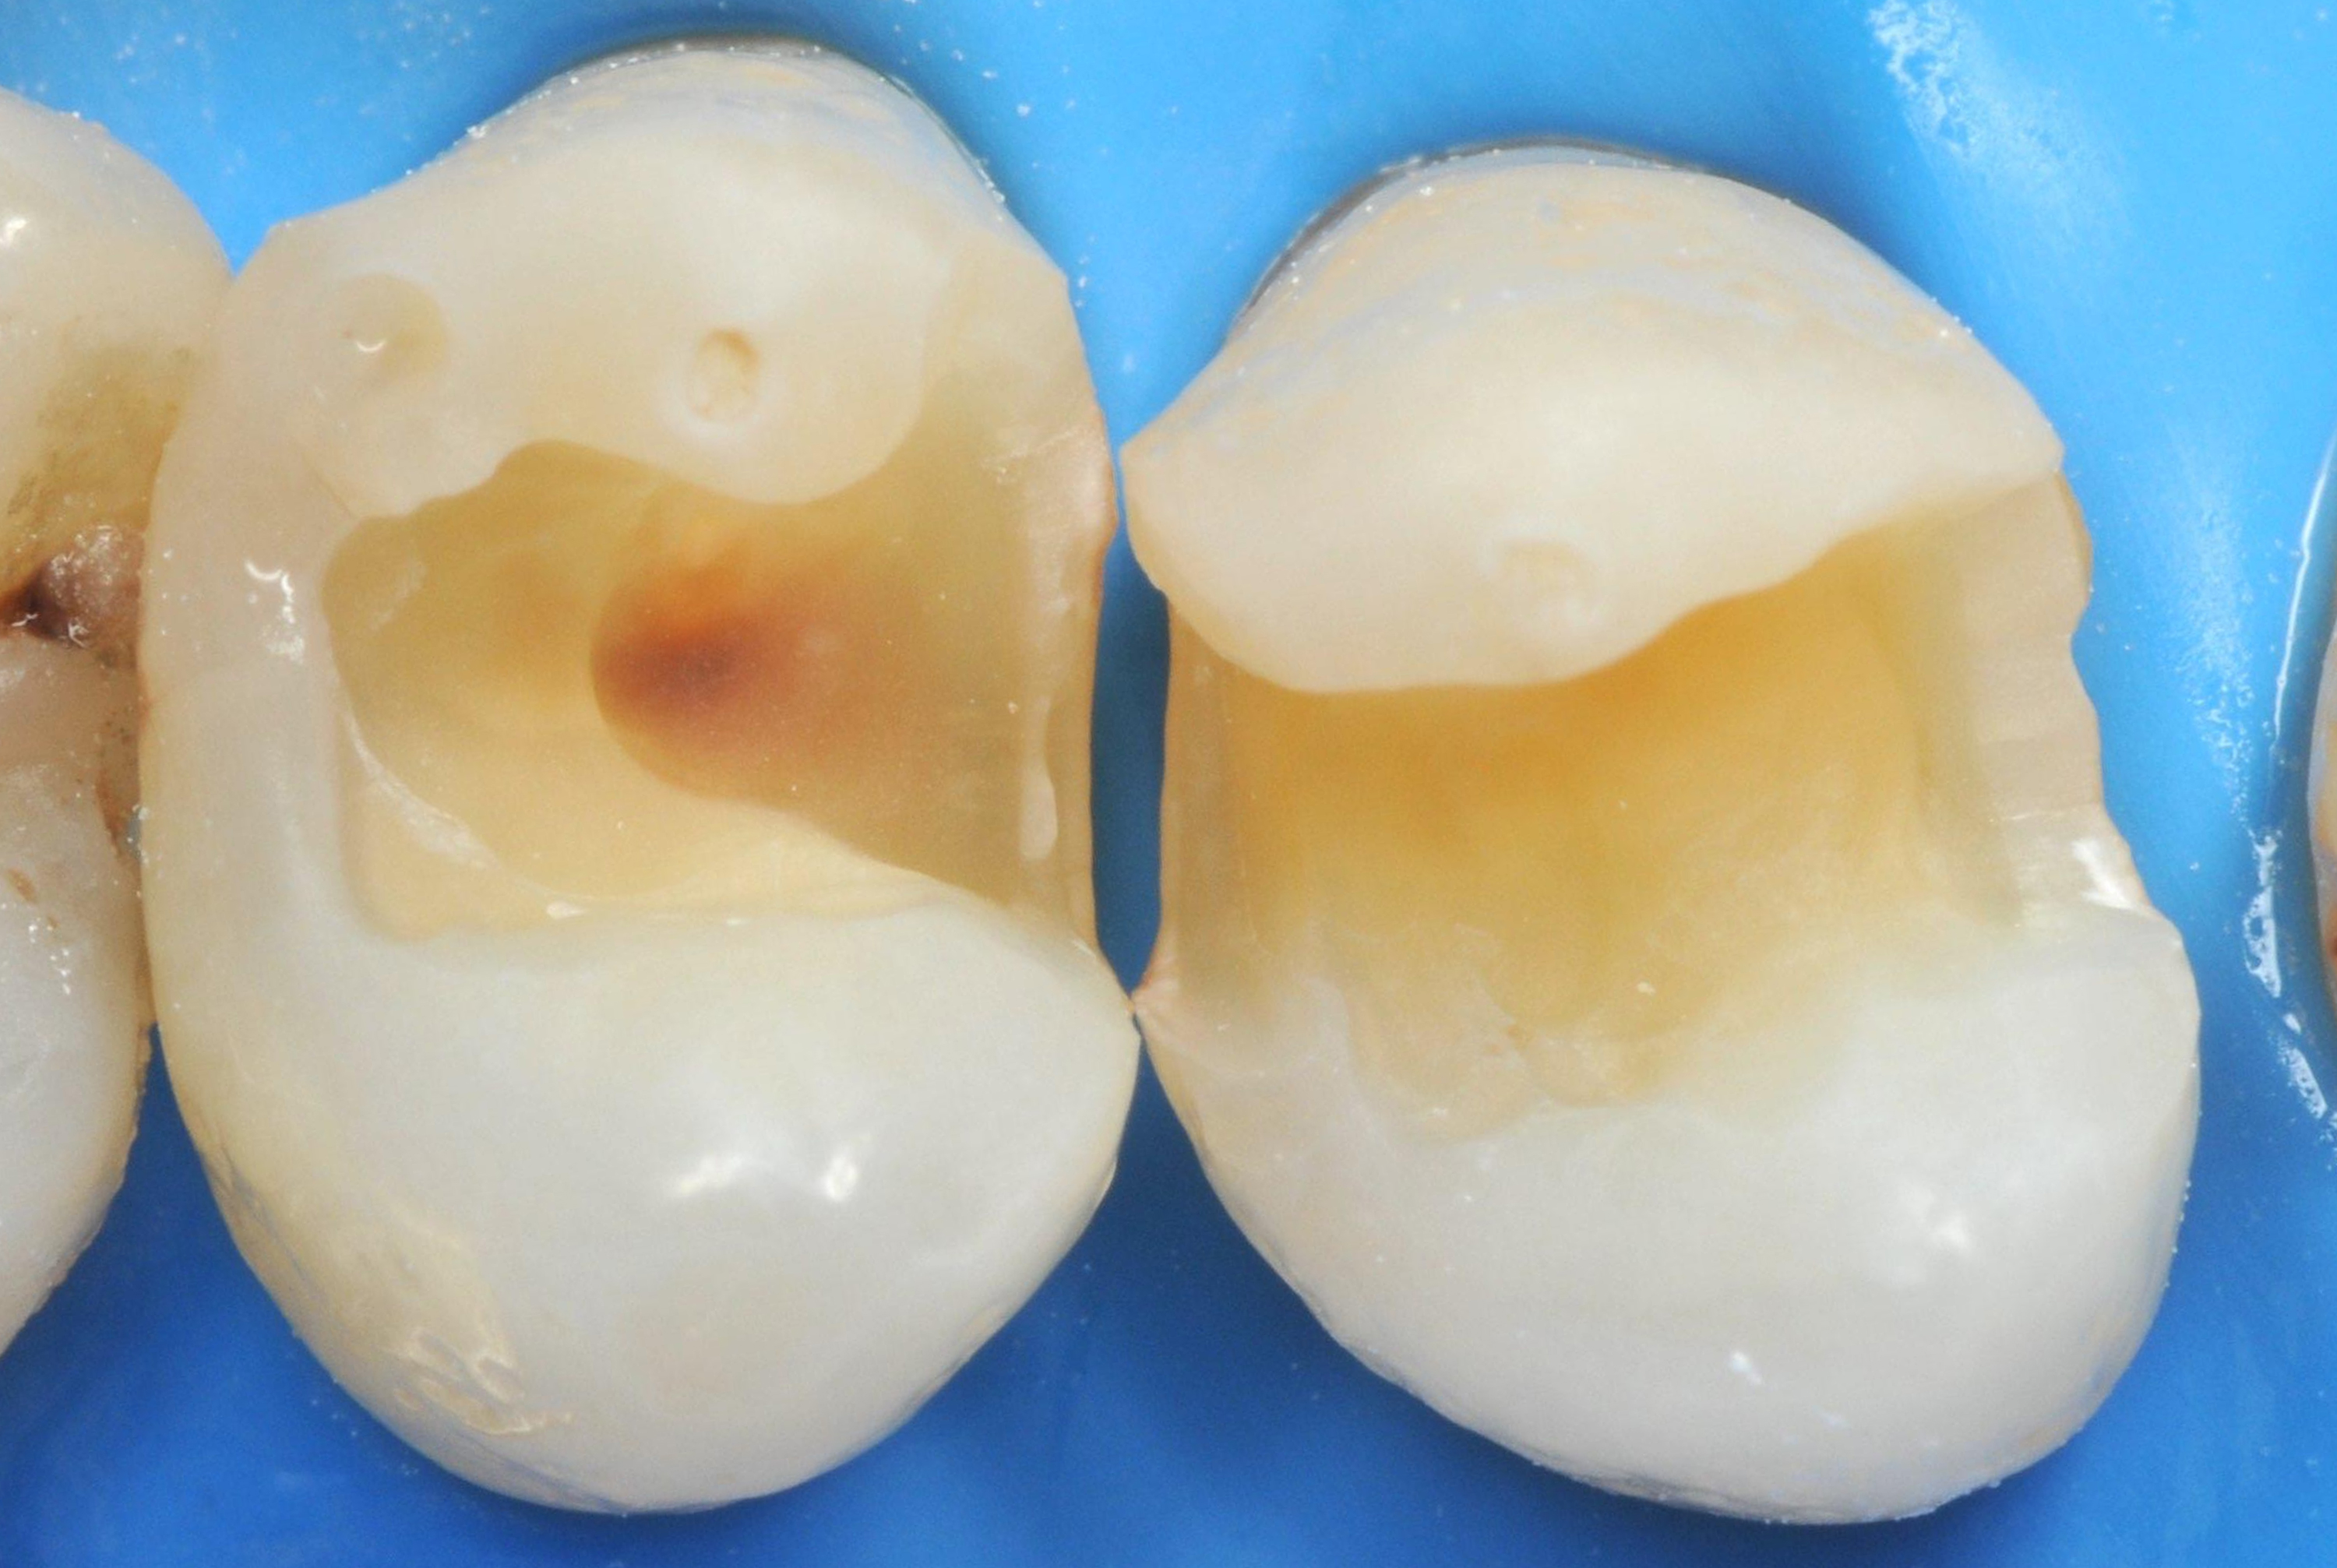

65-letni pacjent zgłosił się z istniejącymi, nieszczelnymi wypełnieniami kompozytowymi, które wymagały wymiany w celu usunięcia zmian próchnicowych i odbudowy struktury zęba (ryc.1).

Po założeniu koferdamu usunięto stare wypełnienia i uzyskano dwa ubytki klasy II (ryc. 2).